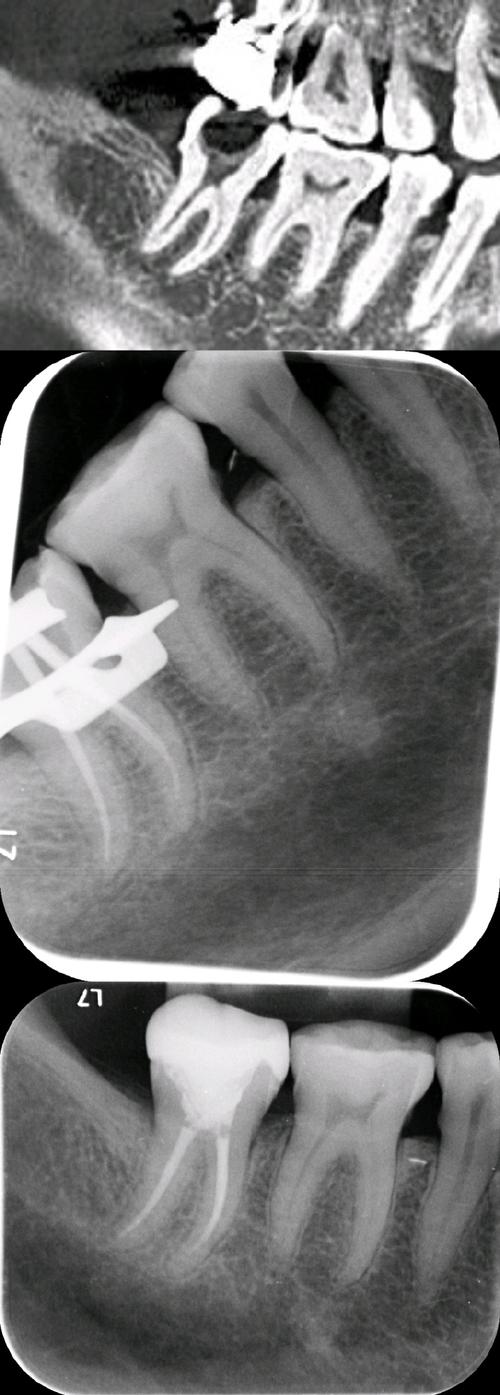

| X线片检查 | 可见根尖周骨质破坏暗影;若存在正畸龋,可见牙体组织低密度影 | 排除根尖周炎,判断牙髓炎症是否扩散;评估正畸装置对牙根及牙槽骨的影响 |

正畸前需进行详细的口腔检查,包括牙髓活力测试(冷热测试、电活力测试)、X线片(曲面断层、根尖片)评估牙根形态、根尖周情况及牙槽骨密度,对存在深龋、牙隐裂、牙髓钙化或根尖周病变的患牙,需先完成根管治疗或充填治疗,再开始正畸,对于糖尿病患者、老年人等高危人群,需控制全身病情,降低牙髓炎症风险。

遵循“轻力矫治”原则,避免使用过大的矫治力(如关闭间隙时采用“滑动法”而非“关闭曲法”,减小每一步的移动量),牙齿移动速度控制在0.5-1mm/月,定期拍摄X线片监测牙根位置及根尖周骨质情况,发现牙根吸收或骨质破坏时,及时调整矫治力,对于需要植入支抗钉的患者,术前需精准定位,避开牙根根尖部,减少对牙髓的机械刺激。

A:通常可以,根管治疗后,患牙失去牙髓的营养供应,牙体组织脆性增加,但只要根管充填完善,无根尖周炎症,且牙根无严重吸收,仍可继续正畸治疗,不过需注意:①治疗后需观察3-6个月,确认根尖周病变稳定(X线片显示根尖暗影缩小或消失)后再恢复矫治;②正畸中需减小矫治力,避免使用过大力量导致牙根吸收或牙体折裂;③对于大面积缺损的患牙,根管治疗后需行桩核冠修复,增强牙体强度,防止治疗中牙折,若根管治疗后出现牙根严重吸收或根尖周病变持续加重,需与正畸医生共同评估,必要时调整治疗方案或终止正畸。